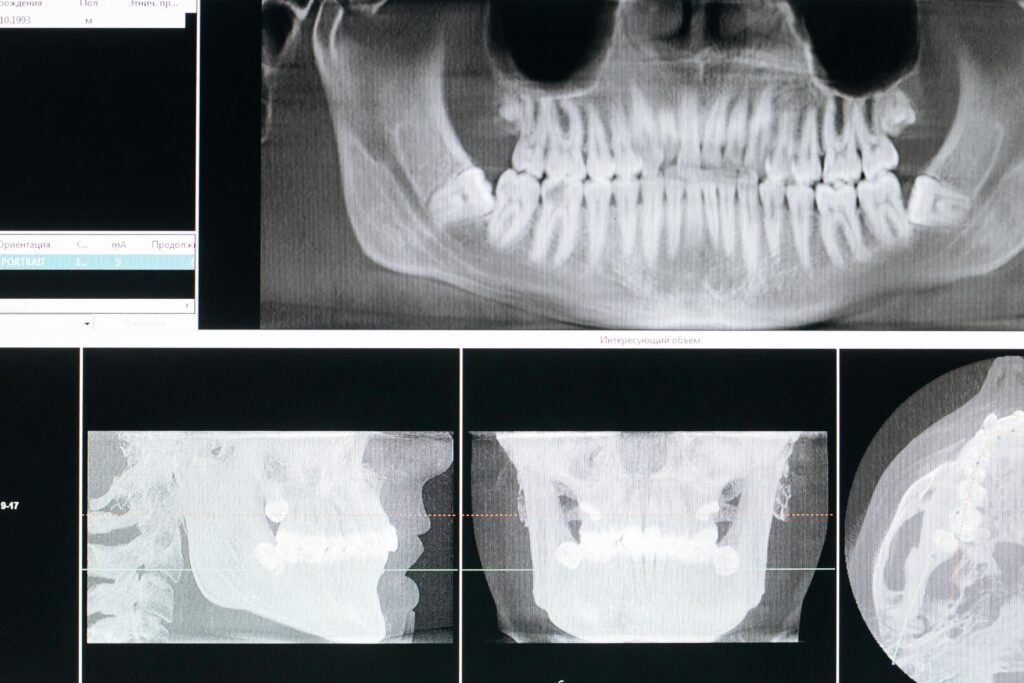

- 3D CT scan (CBCT) — This gives a clear 3D picture of your bone volume

- Digital X-rays

If the scan shows less than 5–8 mm of bone height (depending on location), a bone graft is usually recommended.